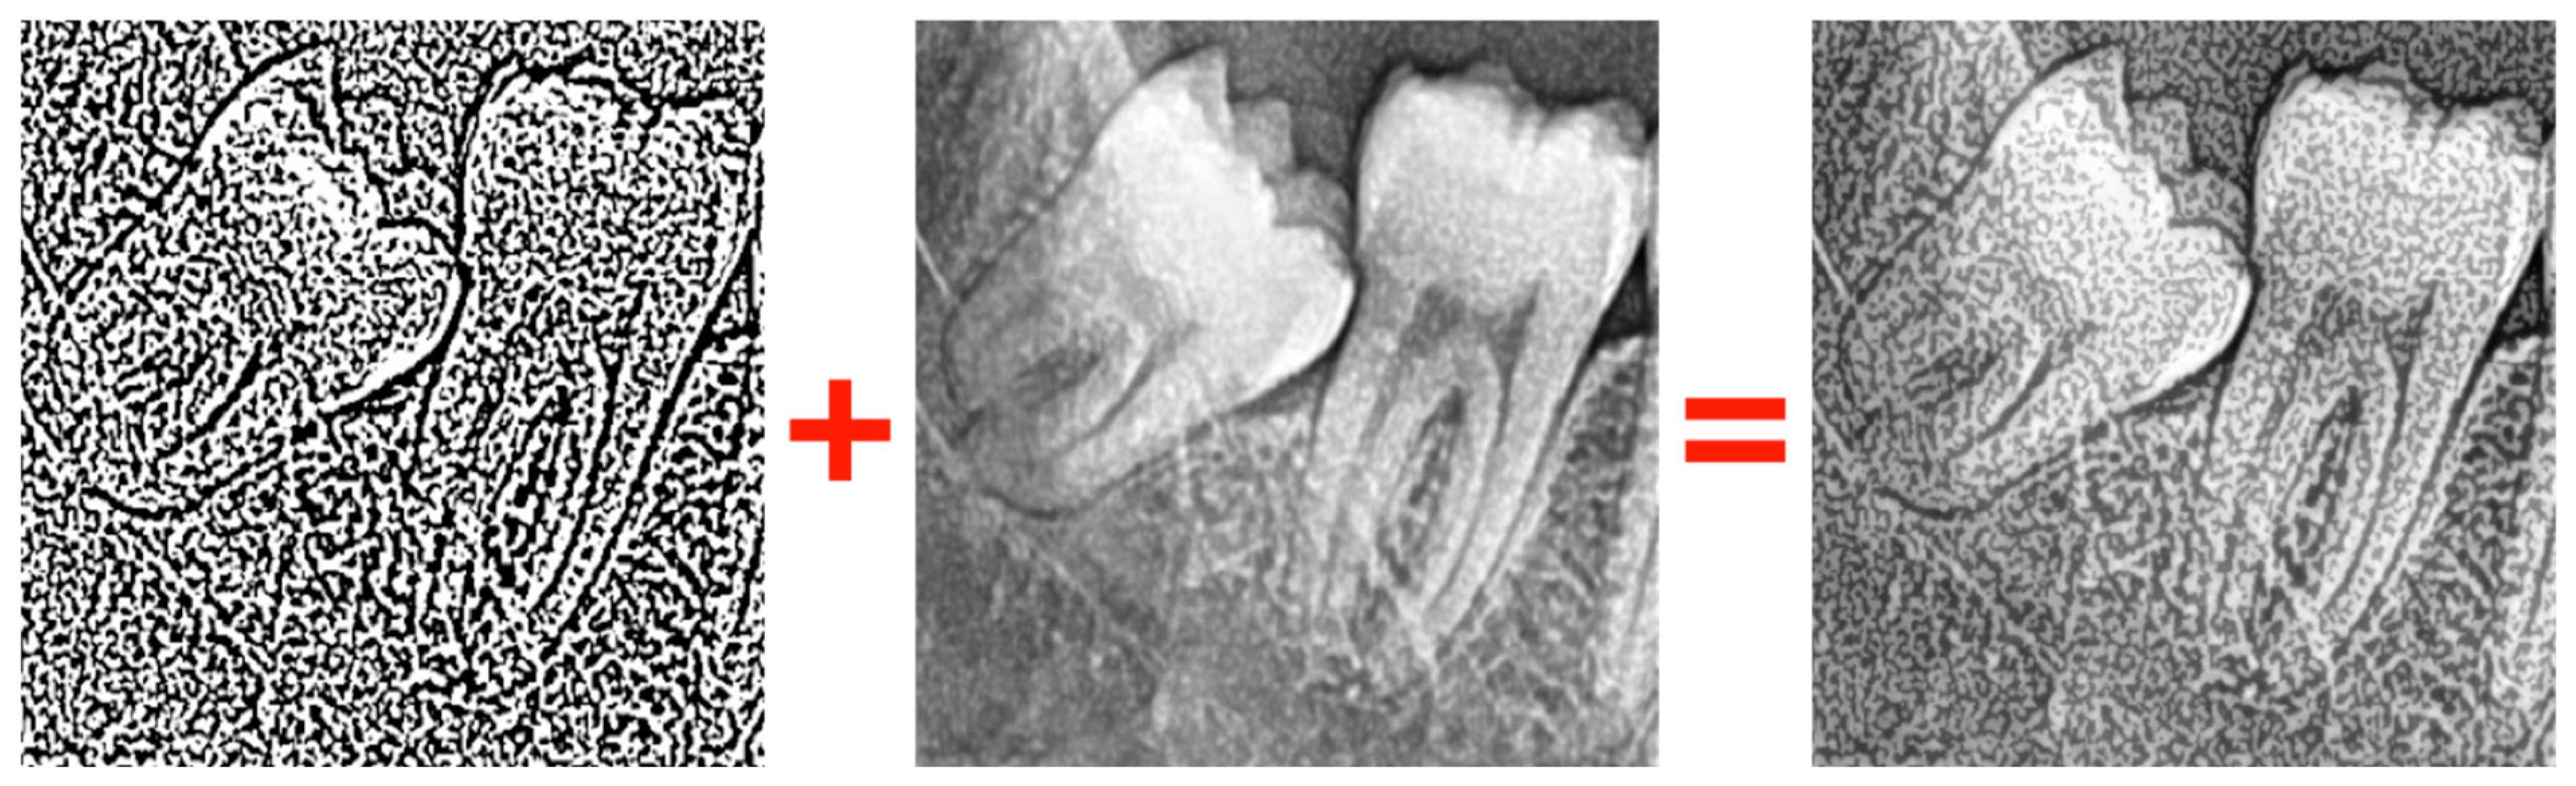

- Gaussian Thresholding: A segmentation method that classifies pixels based on whether they fall above or below a certain threshold (Figure 6).